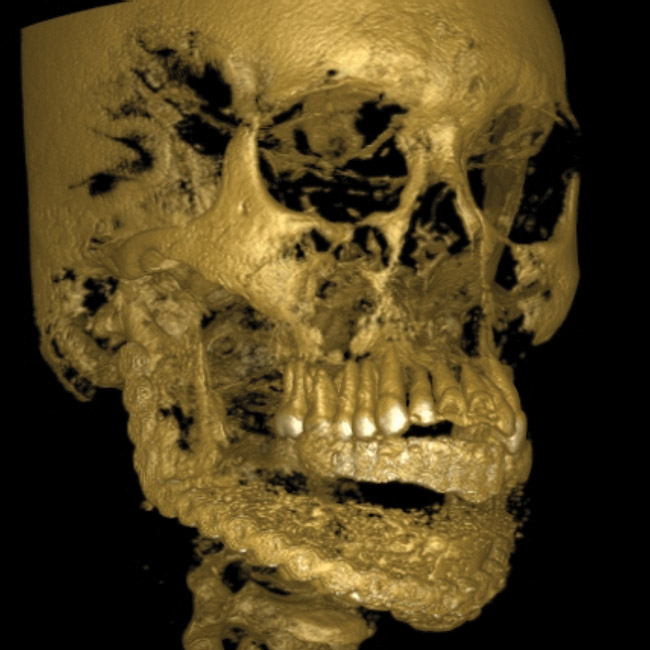

At that appointment, a cone-beam computed tomography (CBCT) scan and other radiographs were obtained. The radiographic findings revealed a multilocular expansile radiolucency that extended further than what was observed in the initial clinical examination. The radiolucency appeared to displace the inferior alveolar canal and lower border and had expanded but not perforated the mandibular cortex (Figure 3). The diagnostic work-up initially consisted of lesion aspiration. Then, multiple pieces were collected by incisional biopsy. The pathology report showed the histologic presence of epithelial islands that mimicked the enamel organ within a fibrous collagenized stroma. There were peripheral columnar cells resembling preameloblasts, a loose arrangement of epithelial cells with squamous metaplasia, and cystic degeneration toward the center (Figure 4). These histopathologic findings were consistent with the diagnosis of primary invasive ameloblastoma.4

Figure 3  Panoramic radiograph shows a multilocular radiolucency extending from the left second molar to the right first molar.

Figure 3